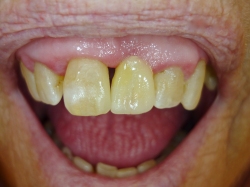

En delprotese kan hjælpe dig, der har mistet nogle af dine naturlige tænder.

Vi sørger for, at du får udfyldt hullerne med tænder, der ligner dine egne — både i farve og størrelse. På denne måde kan du få dit eget naturlige smil tilbage. Kontakt vores klinik for en gratis og uforpligtende forundersøgelse, hvor vi i fællesskab undersøger, hvilken løsning der er bedst for dig, så du kan få et resultat, du er tilfreds med.